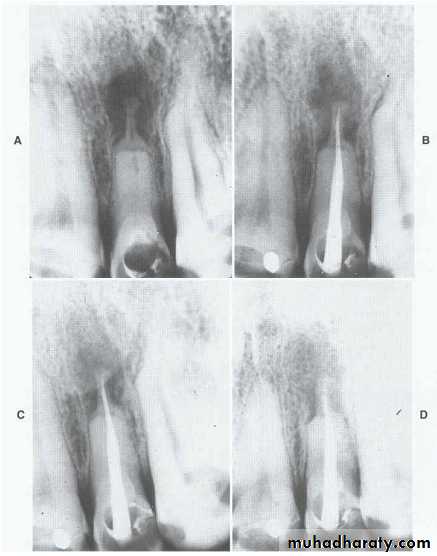

6) Internal root resorption Internal resorption is initiated within the pulp cavity and results in loss of substance from dentinal tissue.EtiologyExact etiology is unknown. Patient often presents with history of trauma, persistent chronic pulpitis, history of pulpotomy, crown preparation, force from orthodontic treatment, impacted teeth,…etc.

• Usually asymptomatic, recognized clinically through routine radiograph (especially in the root)• Pain occurs in cases of perforation of crown.

• “Pink Tooth” is the pathognomic feature of internal root resorption (especially in the crown).

• Radiographic changes:

– Radiolucent enlargement of pulp canal

– Original root canal outline distorted

– Bone changes are seen only when root perforation into periodontal ligament takes place.

• Pulp tests: Positive, though coronal portion of pulp is necrotic, apical pulp could be vital

Treatment

• Pulp extirpation stops internal root resorption.

• Surgical treatment is indicated if conventional treatment fails.